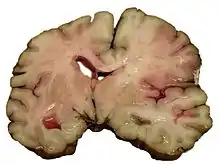

1) نزيف داخل المخ، وهو نزيف داخل الدماغ نفسه (عندما ينفجر شريان في الدماغ، يغمر الأنسجة المحيطة بالدم)، إما بسبب نزيف داخل القصبة (نزيف داخل أنسجة المخ) أو نزيف داخل البطين (نزيف داخل البطين).

النزيف الدماغي

النزيف دماغي هو أحد انماط النزيف الذي يحدث داخل الأنسجة الدماغية مما يُهدد حياة المُصاب ,[41] حيث يتسبب النزيف في تلف الخلايا الدماغية.[5] يحدث النزيف الدماغي بين الدماغ وأحد أغشيته، بين الأغشية الدماغية أو بين الجمجمة والغلاف الدماغي.ترتبط الإصابة بالنزيف الدماغي بعدد من العوامل ومنها: - ارتفاع ضغط الدم. - استخدام العقاقير الدوائية المُضادة لتخثر الدم. - اضطرابات الدم. - الأورام . - التعرض لحادث يؤثر في الرأس. - ام الدم ( انتفاخ أو ضعف الجدران الشريانية ) . - التشوهات الوريدية الشريانية.[5]

النزيفية

يمكن أن يحدث نزيف داخل تجويف الجمجمة لأسباب مختلفة. نزيف تحت الجافية وفوق الجافية هي في معظمها تحدث نتيجة للصدمة.[52] اما السكتات الدماغية النزفية فتحدث داخل الحشوة النسيجيه للدماغ أو مسافات داخل البطين، وتصنف على أساس الأمراض التي تستند إليها. بعض الأمثلة من السكتة الدماغية النزفية هي نزيف الناتج عن ارتفاع ضغط الدم، تمدد الأوعية الدموية، تمزق الناسور AV، تمزق أنيوريسم، والتحول من سكته دماغيه اسكيميه، ونزيف الناتج عن تعاطي المخدرات.[52] وهي تؤدي إلى اصابة وجرح وتشوه الانسجة الناتجة من ورم دموي أو تجمع دموي التي يعمل على الضغط على الانسجة. وبالإضافة إلى ذلك، يمكن للضغط أن يؤدي إلى فقدان تدفق الدم إلى الأنسجة المتضررة، فان الدم الصادرعن نزيف في الدماغ يبدو أن له تأثيرات سامة مباشرة على أنسجة المخ والأوعية الدموية.[36][53] فبالتالي يساهم اصابات ثانوية في الدماغ بعد النزف.[53]